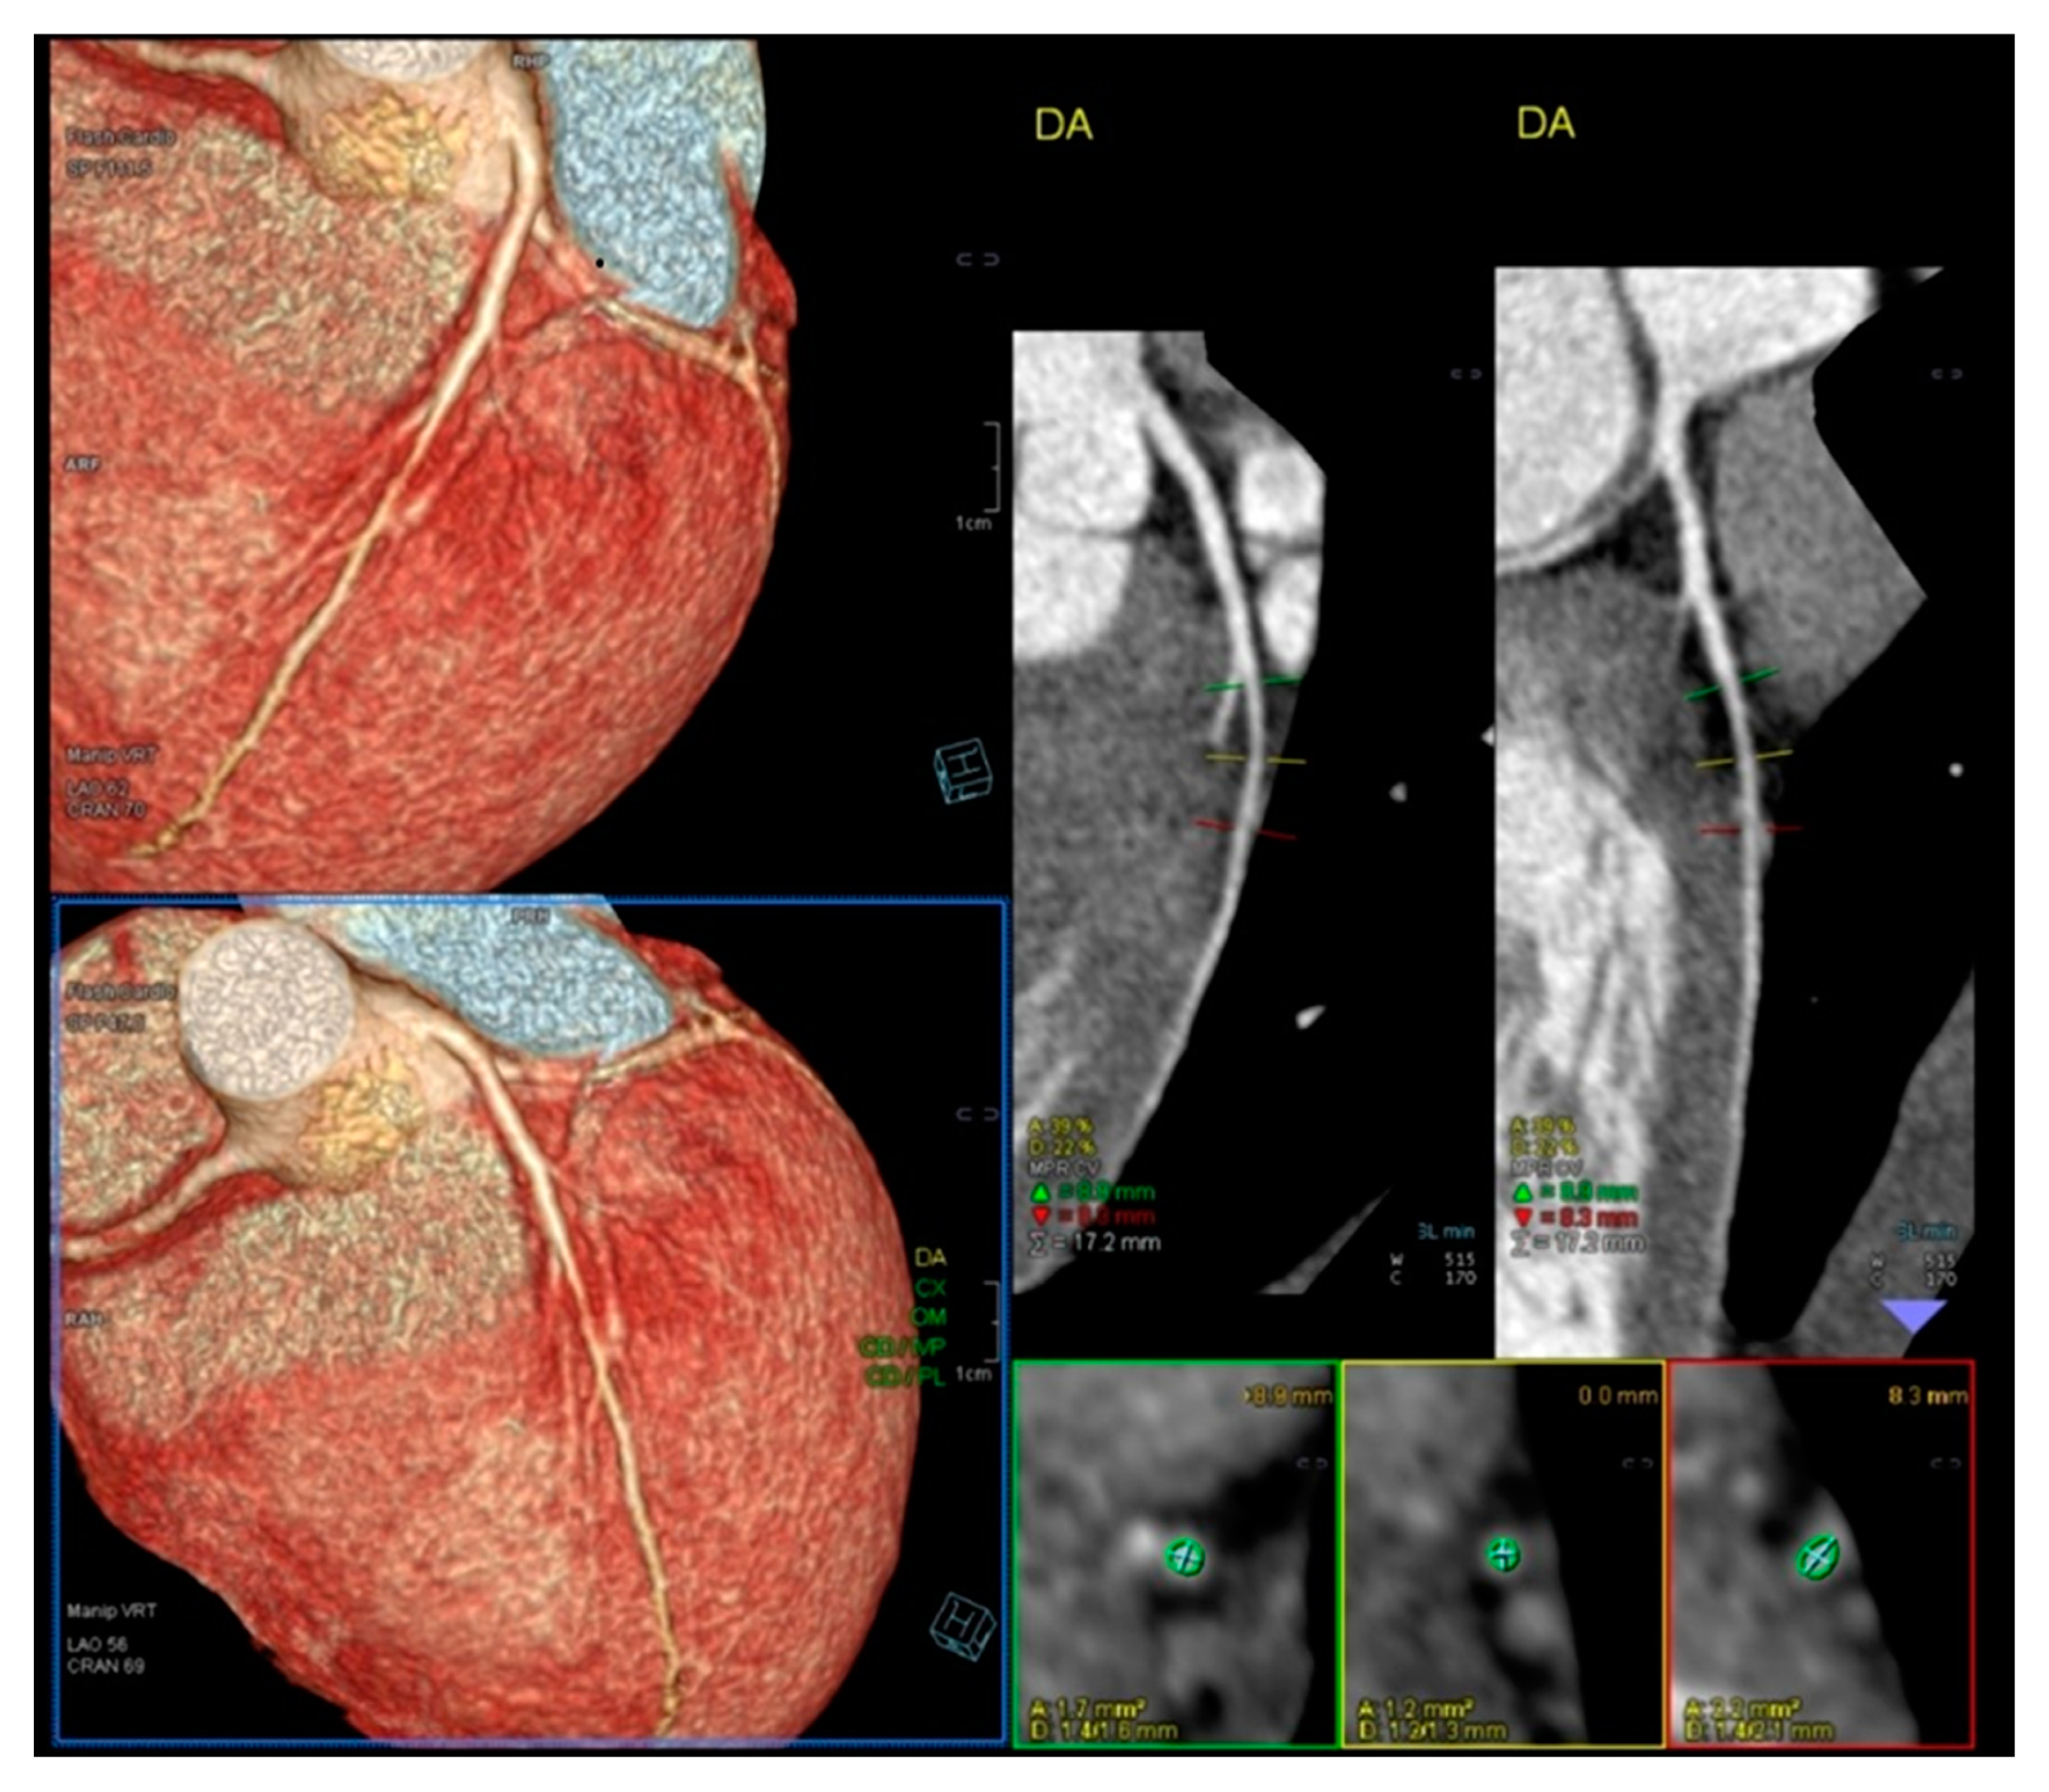

- Lopes, A.; Cotrim, C.; Martins, J.D.; Pinto, F. Exercise-induced intraventricular obstruction in a child with near syncope and chest pain during exercise. Pediatr. Cardiol. 2011, 32, 1032–1035. [Google Scholar] [CrossRef]

- Cotrim, N.; Castilho, B.; Cotrim, C.; Guardado, J.; Baquero, L. An Unexpected Finding in an Adolescent Rowing Athlete With Angina Pectoris—A Case Report. Clin. J. Sport Med. 2024, 35, 242–245. [Google Scholar] [CrossRef]

- Lopes, L.R.; Cotrim, C.; Cruz, I.; Picano, E.; Pinto, F.; Pereira, H. Left ventricular outflow tract obstruction as a primary phenotypic expression of hypertrophic cardiomyopathy in mutation carriers without hypertrophy. Int. J. Cardiol. 2014, 176, 1264–1267. [Google Scholar] [CrossRef]

- Cotrim, C.; Almeida, A.G.; Carrageta, M. Clinical significance of intraventricular gradient during effort in an adolescent karate player. Cardiovasc. Ultrasound. 2007, 5, 39. [Google Scholar] [CrossRef]